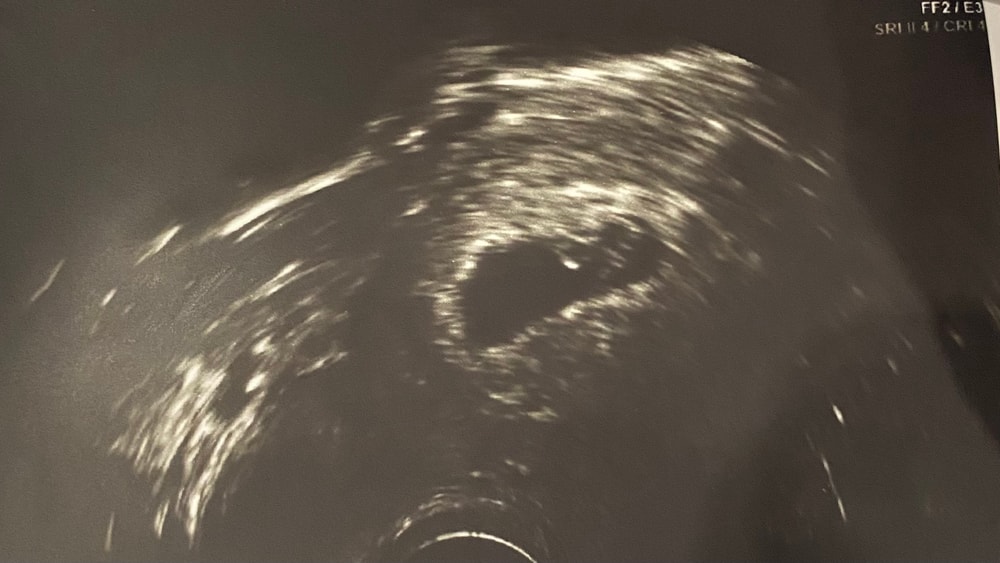

Вчера была на узи (7-8 день задержки) 4 недели 5 дней. Плодное яйцо в полости матки СВД 9.1 мм, эмбрион и жм пока не визуализируется, и вот размер нормальный НО! Она сказала, что нет желтого тела ни на одном яичнике…я очень надеюсь, что она каким-то образом просто его не увидела, завтра к гинекологу утром. Безумно стала пер